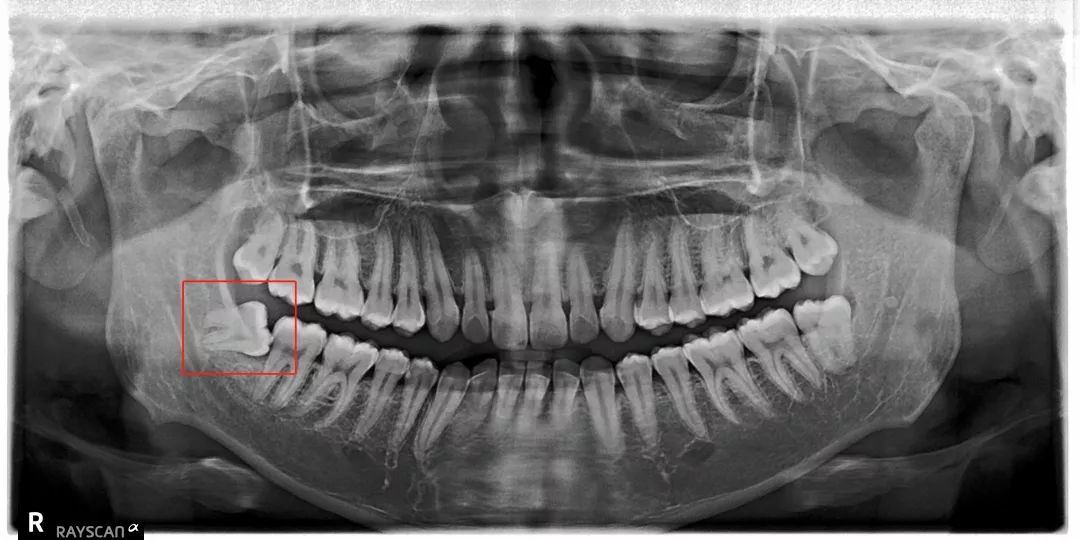

科普一波智齿~

但是有部分智齿会顽强抵抗

比方说像树根一样长出很多「根」

扎根在骨头里,死死抓住

➋ 挖地三尺